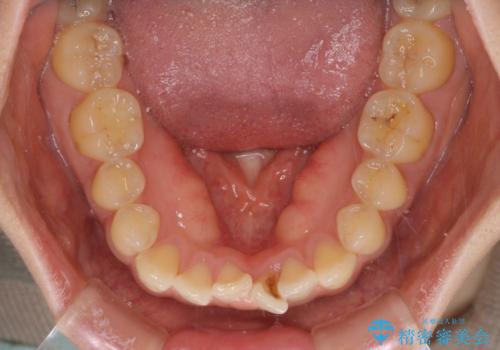

- 前歯のデコボコと上下前歯の隙間を気にして来院された患者様です。

下顎前歯はデコボコのため、歯肉が腫れやすくなっていました。

また、舌突出癖のため、上下前歯の間に隙間ができてしまい、上顎前歯が前方に傾斜している状態でした。

舌突出癖改善のためのトレーニングを行いながら、インビザラインにて矯正治療を行うこととしました。